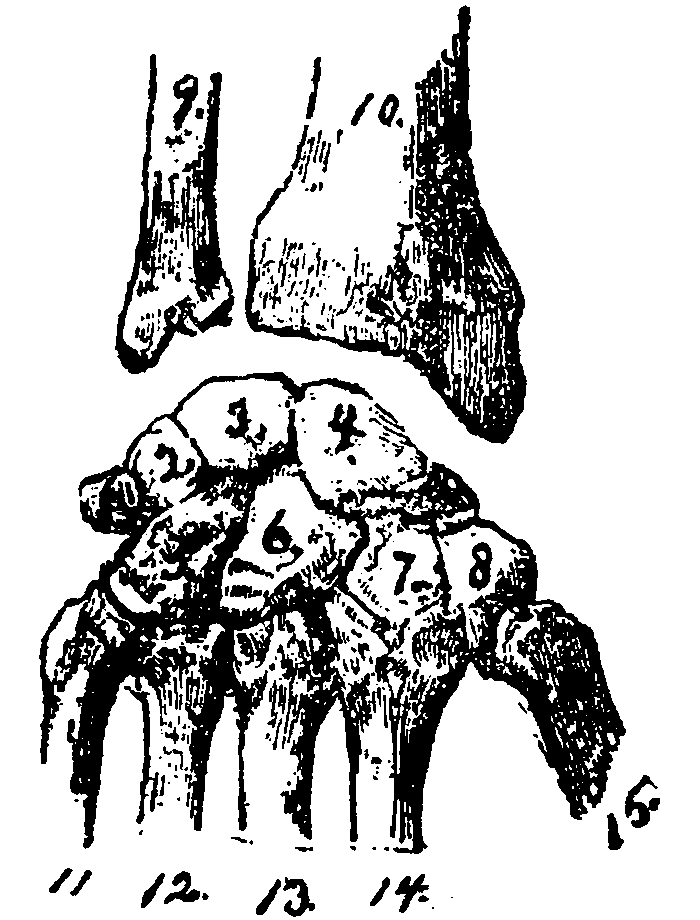

FIG. A.

FIG. A.

1, 2, 3, 4, the upper row of the bones of the wrist.

5, 6, 7, 8, the lower row of the bones of the wrist.

9, 10, the lower ends of the bones of the fore-arm.

11, 12, 13, 14, 15, the upper ends of the bones of the palm of the hand.

The bones of the wrist are so firmly fastened together that they are seldom put out of place. The upper row joins with the bones of the fore-arm, the lower with those of the palm of the hand.